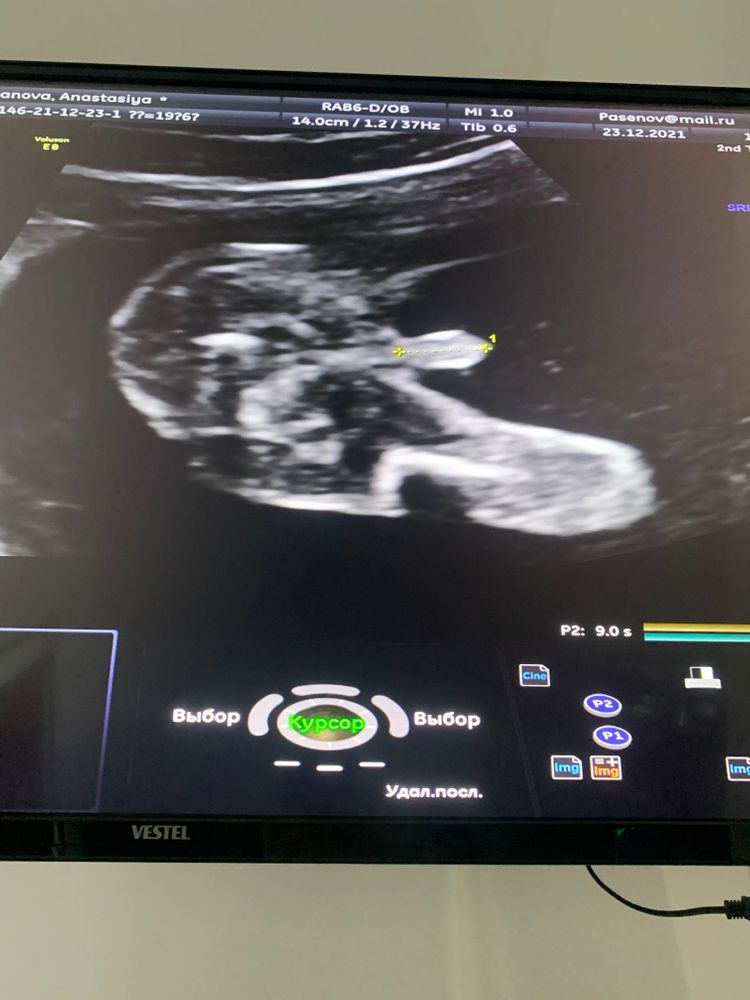

На цервикометрии подтвердили пол 💙

Kotya, я сегодня испытала культурный шок, глядя на это достоинство на экране 😂

Kotya, вот вам мое , вид снизу 😁 Изображение

Karmilla, 😁его еще и замерили, как я понимаю.

Kotya, для наглядности 🤣🤣🤣